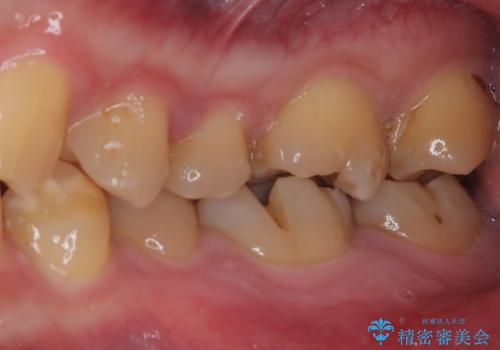

- 食事中に奥歯が痛むとのことで来院された患者様です。

レントゲンやCTより、深くまで破折していることが分かり、抜歯が必要な状態でした。

歯槽骨の状態は良好であったため、抜歯即時埋入インプラントによる補綴治療を行うこととしました。